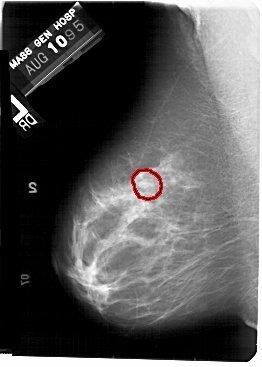

A_1445_1.LEFT_CC

LEFT_CC LINES 5401 PIXELS_PER_LINE 3916 BITS_PER_PIXEL 12 RESOLUTION 43.5 OVERLAY

FILE: A_1445_1.LEFT_CC.OVERLAY

TOTAL_ABNORMALITIES 1

ABNORMALITY 1

LESION_TYPE MASS SHAPE ROUND MARGINS OBSCURED

ASSESSMENT 3

SUBTLETY 2

PATHOLOGY BENIGN

TOTAL_OUTLINES 1

BOUNDARY